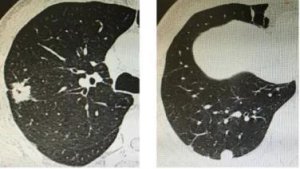

【公益一院】传承优势,肺结节多学科门诊化解群众“急难愁盼”就诊难题

随着低剂量胸部CT的广泛应用及人民群众健康查体的普及,肺部结...

【一院·技术】直达肺内结节,“导航定位”之下实施精准诊疗

随着人们健康意识的提高及CT的普及,特别是开展低剂量CT筛查...